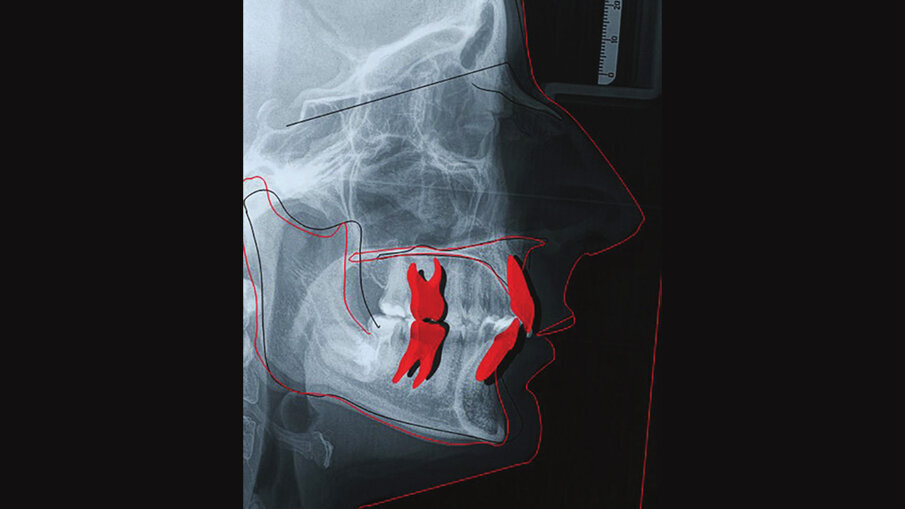

Lo stripping (Figg. 7a-7e) è stato necessario per la risoluzione dell’affollamento in arcata superiore, ma soprattutto per recuperare spazio in arcata inferiore; non potendo proclinare ulteriormente gli incisivi inferiori oltre la sinfisi, è stato necessario recuperare spazio inferiormente, assicurandoci che le radici fossero sempre all’interno della midollare. Questa condizione non ci ha permesso di avere una risoluzione completa del morso profondo che si sarebbe potuta avere sfruttando l’intrusione relativa, dovuta proprio alla proclinazione anteriore degli incisivi, sommata all’intrusione assoluta degli stessi e all’estrusione posteriore. Nonostante questo, l’utilizzo dei bite-ramp anteriori e la pianificazione di attachments rettangoli orizzontali bisellati a seconda del movimento da ottenere (intrusione frontale ed estrusione posteriore) è stata raggiunta una discreta e accettabile apertura del morso, con un ritorno dell’overbite verso valori nella norma (Figg. 9a-9c).

Figg. 9a-9c_Esami radiografici dopo il trattamento, con sovrapposizione sul piano SN. Questo ci mostra come, non potendo proclinare ulteriormente gli incisivi inferiori oltre la sinfisi per sfruttare l’intrusione relativa, l’apertura del morso è stata ottenuta sfruttando al massimo solo movimenti di intrusione assoluta, seppur minimi, e movimenti di intrusione relativa superiore ed estrusione posteriore parziale, considerando la difficoltà di quest’ultima, a causa della tipologia brachifacciale della paziente.

Figg. 9a-9c_Esami radiografici dopo il trattamento, con sovrapposizione sul piano SN. Questo ci mostra come, non potendo proclinare ulteriormente gli incisivi inferiori oltre la sinfisi per sfruttare l’intrusione relativa, l’apertura del morso è stata ottenuta sfruttando al massimo solo movimenti di intrusione assoluta, seppur minimi, e movimenti di intrusione relativa superiore ed estrusione posteriore parziale, considerando la difficoltà di quest’ultima, a causa della tipologia brachifacciale della paziente.

Figg. 9a-9c_Esami radiografici dopo il trattamento, con sovrapposizione sul piano SN. Questo ci mostra come, non potendo proclinare ulteriormente gli incisivi inferiori oltre la sinfisi per sfruttare l’intrusione relativa, l’apertura del morso è stata ottenuta sfruttando al massimo solo movimenti di intrusione assoluta, seppur minimi, e movimenti di intrusione relativa superiore ed estrusione posteriore parziale, considerando la difficoltà di quest’ultima, a causa della tipologia brachifacciale della paziente.

Figg. 9a-9c_Esami radiografici dopo il trattamento, con sovrapposizione sul piano SN. Questo ci mostra come, non potendo proclinare ulteriormente gli incisivi inferiori oltre la sinfisi per sfruttare l’intrusione relativa, l’apertura del morso è stata ottenuta sfruttando al massimo solo movimenti di intrusione assoluta, seppur minimi, e movimenti di intrusione relativa superiore ed estrusione posteriore parziale, considerando la difficoltà di quest’ultima, a causa della tipologia brachifacciale della paziente.